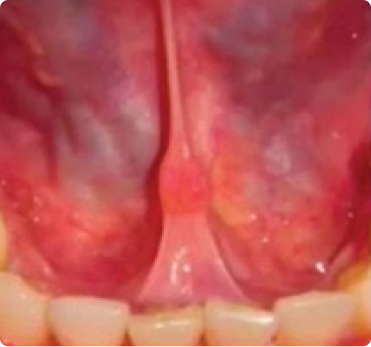

White Light Examination

Under VELscope

Bacterial infections appear red

Yeast infections appear yellow/orang

Porphyrins, byproducts of bacterial metabolism, absorb the VELscope’s blue light and re-emit it as red autofluorescence.​

Yeast cells contain molecules that fluoresce yellow or yellow-orange under VELscope